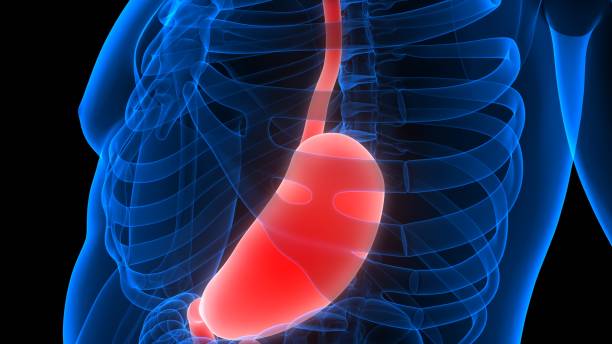

2. 속이 쓰림과 소화 불량

위암 환자들은 종종 속이 쓰리고 소화가 잘 안 된다는 불편함을 느낍니다.

하지만 이러한 증상은 위암에 특이적인 것이 아니며, 다른 소화기 질환에서도 나타날 수 있습니다.

따라서 속이 쓰리거나 소화가 원활하지 않을 때에도 위암을 의심해봐야 합니다.